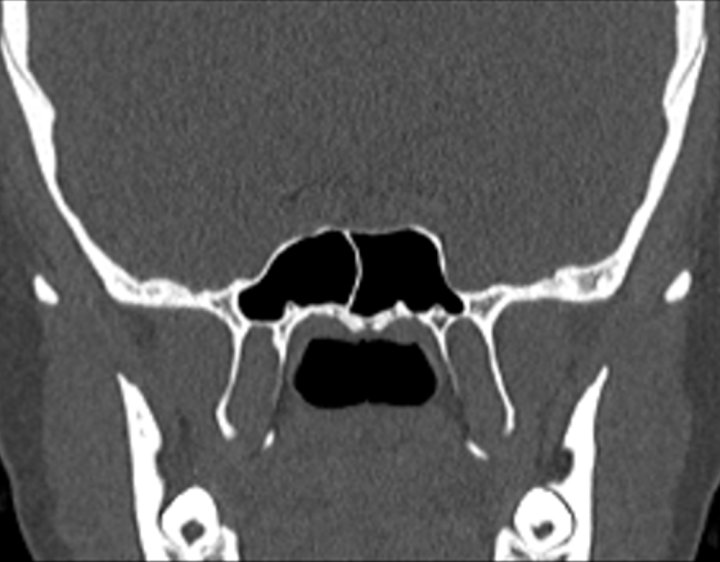

Click any image for labels.